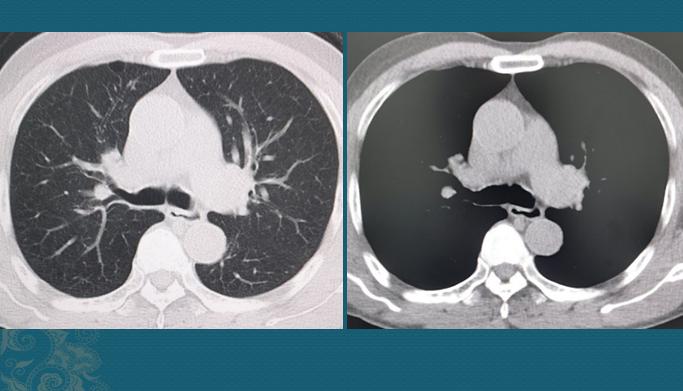

白肺可以治愈,全面治疗总体可分为3个步骤:明确病因 “白肺”是医学影像学上对肺部疾病表现的描述,指患者在胸部X线或CT检查下、本来正常时肺组织表现为“黑色”的部分变白了,一般预示着比较严重的肺炎表现。治疗“白肺”的关键在于寻找病因并进行及时有效的综合治疗。